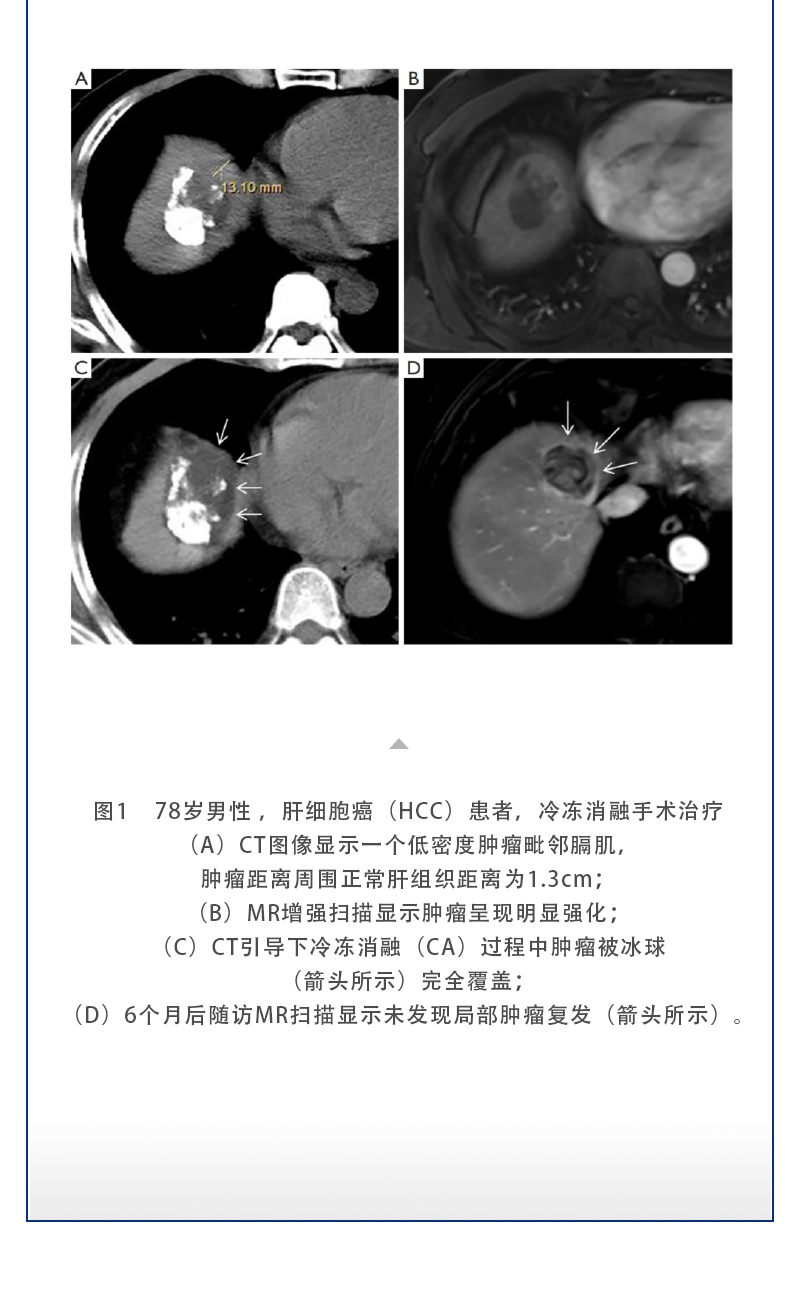

【HYGEA·科研資訊】冷凍消融治療肝癌